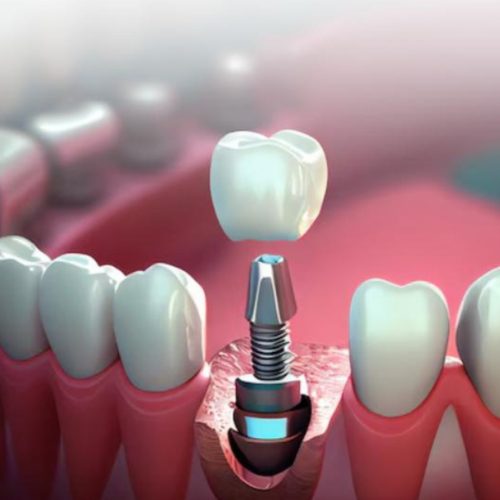

Dental Implants – A Permanent Solution for Missing Teeth

What Are Dental Implants?

A dental implant is a small, biocompatible titanium fixture that functions as an artificial tooth root. It is surgically placed into the jawbone, where it fuses naturally and provides a stable foundation for a crown, bridge, or denture. This makes it the closest alternative to a natural tooth.

Success & Reliability

Dental implants are highly successful, with studies showing a 90–95% success rate when placed under proper protocols. With good care, they can last 25 years or more, offering a long-term solution for missing teeth.

Benefits of Dental Implants

- Longevity & Durability: Designed to last for decades while maintaining strength and function.

- Natural Appearance: Custom restorations blend seamlessly with your smile.

- Prevents Bone Loss: Implants stimulate the jawbone, preventing shrinkage and facial sagging.

- Protects Oral Health: Keeps neighboring teeth from shifting into gaps.

- Improves Function: Restores bite force and makes eating comfortable again.